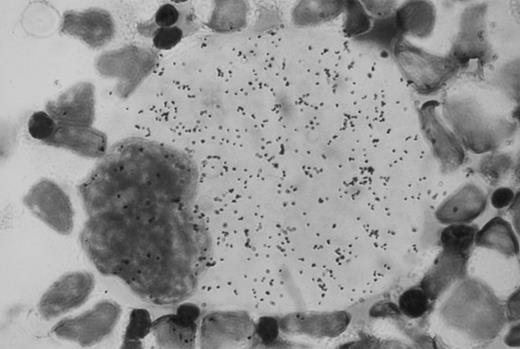

Autoradiographic analysis of 125I-Tpo binding to normal human bone marrow cells showed many grains associated with megakaryocytes (Fig 1). These grains were absent when the cells were incubated with 125I-Tpo in the presence of excess unlabeled Tpo. Grain counts showed that there were an average of approximately 1,300 grains per megakaryocyte in the presence of 125I-Tpo, and 200 grains per megakaryocyte in the presence of 125I-Tpo plus excess unlabeled Tpo. Thus, there were approximately 1,100 specifically bound grains per megakaryocyte. There was no detectable specific binding of 125I-Tpo to morphologically recognizable erythroblasts or myeloblasts. Parallel autoradiographic analysis of 125I-Tpo binding to the murine lymphoblastoid cell line BaF3 transfected with human Mpl receptor (BaF3-MplR cells) showed an average of 10 specifically bound grains per cell.

Autoradiographic analysis of 125I-Tpo binding to normal human bone marrow mononuclear cells. Original magnification × 100.